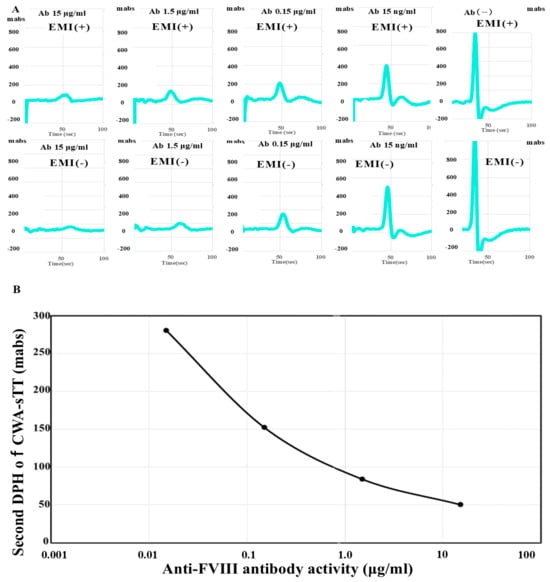

Anti-FVIII antibody activity: Measuring FVIII activity using CWA-sTT enables sensitive detection of residual FVIII activity in patients with AiFVIIID. The measured residual FVIII activity was converted into the amount of FVIII antibody added to normal plasma. Because CWA-sTT shows a similar pattern in normal plasma regardless of the presence of emicizumab, it can be used to measure FVIII activity in the presence of emicizumab. When anti-FVIII antibodies were added, the peak height of the second derivative curve in the CWA-sTT during FVIII activity measurement correlated with the anti-FVIII antibodies in a dose-dependent manner. Therefore, in the FVIII activity measurement system using CWA-sTT, anti-FVIII antibody activity could be evaluated in the range of 0.02 μg/mL to 10 μg/mL regardless of the presence of emicizumab (Figure 2).

Figure 2.

CWA-sTT for various anti-FVIII antibody concentrations (A) and Standard curve for anti-FVIII antibody concentration using CWA-sTT. (A): Upper section, with emicizumab; lower section, without emicizumab; CWA-sTT, clot waveform analysis–clotting time using a small amount of thrombin; FVIII, clotting factor VIII; Ab, antibody; EMI, emicizumab; DPH, derivative peak height; light blue, second derivative curve (acceleration); Regardless of the presence of emicizumab, CWA-sTT shows a pattern dependent on anti-FVIII antibody levels; CWA-sTT can be used to measure anti-FVIII antibody titers in the presence of emicizumab. (B): Standard curve for the anti-FVIII antibody activity. FVIII activity in the presence of emicizumab was measured using CWA-sTT as previously reported [26]. The second derivative peak height of CWA-sTT in normal plasma diluted tenfold with FVIII-deficient plasma shows linearity across FVIII levels from 0.1% to 100%.